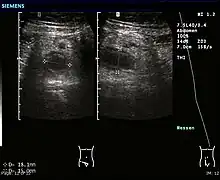

- l’échographie apporte des arguments de diagnostic différentiel, et aide au diagnostic d’abcès appendiculaire ;

Appendicite aiguë perforée

Scanner abdominal : distension de l'appendice, infiltration de la graisse péri appendiculaire, pneumopéritoine localisé - l'IRM abdominale est également très fiable pour le diagnostic[56].